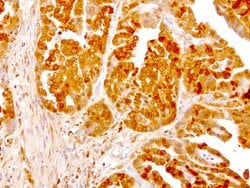

NME1 Mouse anti-Canine, Human, Rat, Clone: UMAB94, liquid, UltraMAB™

NME1 was identified because of its reduced mRNA transcript levels in highly metastatic cells. Nucleoside diphosphate kinase (NDK) exists as a hexamer composed of ′A′ (encoded by this gene) and ′B′ (encoded by NME2) isoforms. Mutations in the gene have been identified in aggressive neuroblastomas. Two transcript variants encoding different isoforms have been found for this gene. Co-transcription of this gene and the neighboring downstream gene (NME2) generates naturally-occurring transcripts (NME1-NME2), which encodes a fusion protein comprised of sequence sharing identity with each individual gene product.Specifications

| Immunocytochemistry, Immunofluorescence, Immunohistochemistry (Paraffin) | |